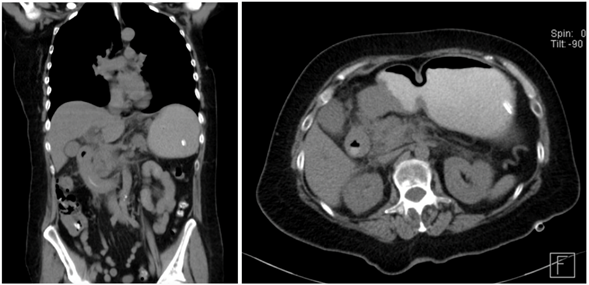

On her first day, the patient presented decreased pain at the epigastric level, she had a nasogastric tuve that reported an output of 300cc with no characteristic of gastro alimentary or intestinal debris, clear liquid with slight hematic debris was observed. Laboratories: Potassium 4.5, Sodium 145, Chloride 105.2, Leukocytes 16, Creatinine 1.6. An abdominal tomography was performed, reporting blastic lesions in vertebral bodies and iliac bone, thickening of the duodenal arch and part of the jejunum, the rest of the intestine without evident data of alterations + diverticulosis without data of complication (Figure 3).

Figure 3 Computed tomography: blastic lesions in vertebral bodies and iliac bone, thickening of the duodenal arcade and part of the jejunum, rest of intestine without evident data of alterations.